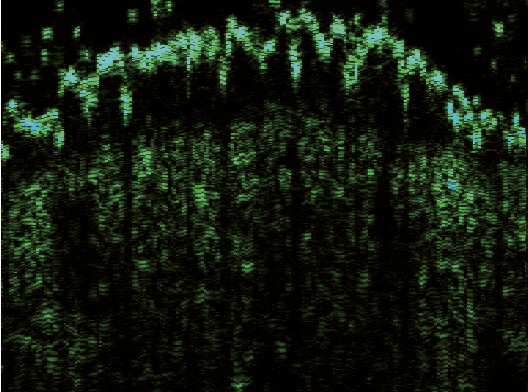

Эпидермис в очагах ББ определялся в виде полосы высокой эхогенности белого цвета с многочисленными желтыми и синими вкраплениями и в виде полосы зеленого оттенка, расположенной под ней. Его внутренний контур был четким и хорошо отграниченным от подлежащей дермы. В зависимости от ультрасонографической картины эпидермиса сканограммы очагов ББ были разделены на две разновидности. В 6 (75%) случаях (1-я разновидность) очаги представляли собой гиперэхогенную полосу неравномерной толщины, волнообразной формы с почкообразными отростками вглубь дермы (рис. 2). В 2 (25%) случаях (2-я разновидность) регистрировали гиперэхогенный слой одинаковой ширины на всем протяжении, с ровным внешним и внутренним контуром (рис. 3).

Рис. 2. Сканограмма болезни Боуэна (датчик 75 МГц). Гиперэхогенный эпидермис неравномерной толщины и волнообразной формы с почкообразными отростками вглубь дермы (разновидность 1). Гипоэхогенная зона определяется в виде образования полосовидной формы с четкими границами